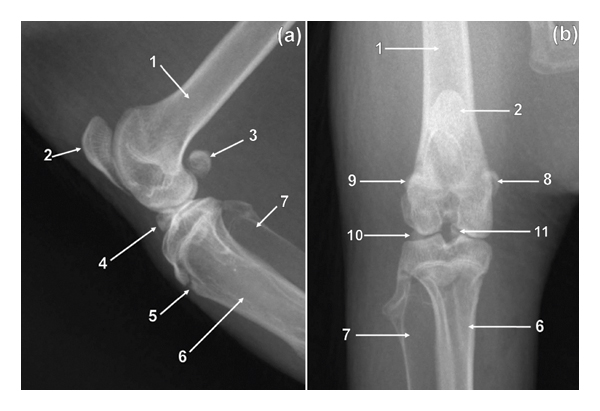

3.6. Sesamoid Bones

The patella had a sharp and extended apex (Figure 6). The former had a tuberosity on the cranial surface (Figure 6(a)). The tuberosity of the patella was seen as an area of increased bone opacity on the ML view (Figure 6(a)). The patella was poorly visualised on the CdCr view of the stifle as a result of its superimposition on the distal third of the body of the femur (Figure 6(b)). A tarsal sesamoid bone was visualised in all cane rats (Figures 4 and 5). The tarsal sesamoid bone appeared comma shaped on the PlD view (Figure 4). Lateral and medial sesamoid bones of the gastrocnemius muscle (lateral and medial fabellae) were seen in all animals (Figure 6). The two fabellae were visualised superimposed on the ML view (Figure 6(a)). Each metatarsophalangeal joint of digits II–V had paired proximal sesamoid bones (Figure 5(a)). In addition, each distal interphalangeal joint of digits II–V had a distal sesamoid bone (Figure 5(b)). The mineralized sesamoid bone for the popliteal muscle was not seen (Figure 6).

In male greater cane rats, the os penis was visualised on the ML view of the femur (Figure 2(b)). The bone was visualised as a fusiform area of bone opacity elongated craniocaudally (Figure 2(b)). Ossicles were observed in the medial and lateral menisci of the stifle joint in all specimens (Figure 7). The former were located in the cranial horn of the medial and lateral menisci (Figure 7). On the proximodistal view, the medial meniscal ossicle appeared triangular shaped with a trabecular pattern (Figure 7), whereas the lateral meniscal ossicle appeared ovoid shaped with a trabecular pattern (Figure 7). The medial meniscal ossicle was larger than the lateral meniscal ossicle (Figure 7). The lateral and medial meniscal ossicles were superimposed and appeared as a triangular area of bone opacity in the cranial part of the joint on the ML view (Figure 6(a)). The lateral and medial meniscal ossicles were poorly visualized due to their superimposition on the femur and tibia on the CdCr view of the stifle (Figure 6(b)).